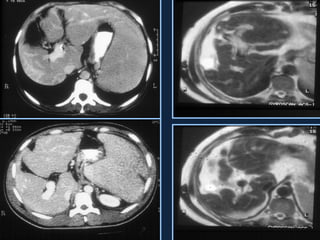

SÍNDROME DE BUDD-CHIARI

• Obstrução da drenagem venosa

hepática no plano das veias

hepáticas ou da VCI.

• Associada às síndromes

mieloproliferativas, trauma, HPN,

carcinoma hepatocelular, gravidez e

uso de anticoncepcionais.

• Ascite, hipertrofia do lobo caudado,

hipertensão portal, aspecto “em

mosaico” do parênquima hepático.

Distribuição perivascular

• Budd-Chiari

– Aumento do lobo

caudado

– Atrofia do restante do

parênquima

• “Compressão

periférica”

– Nódulos regenerativos

•  T1

• ,  ou  T2